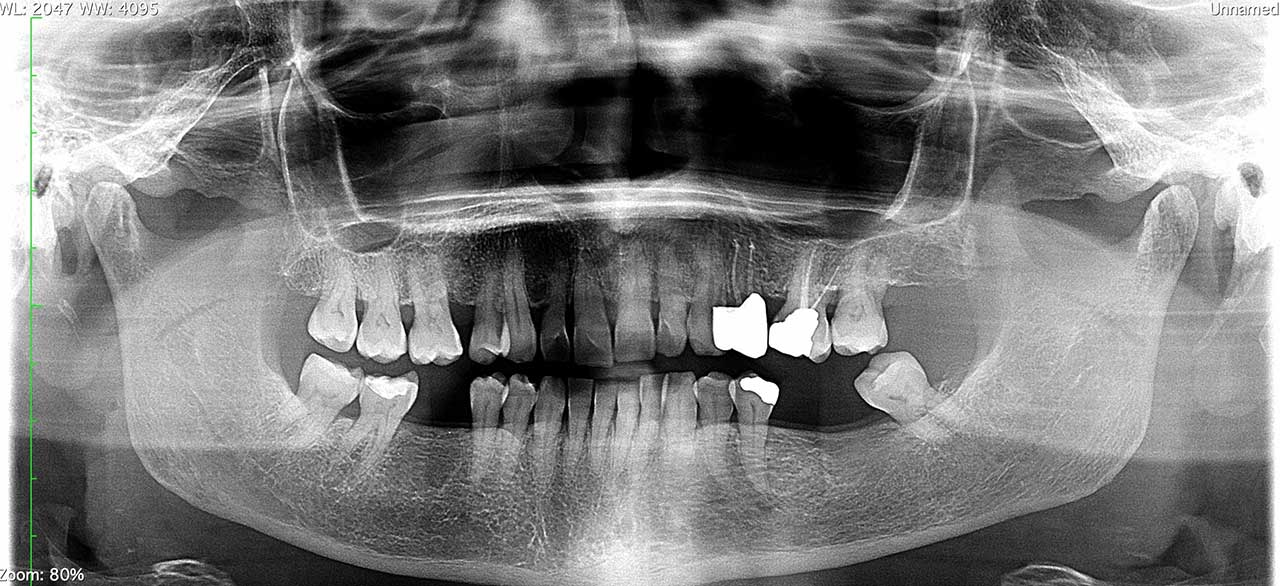

OPT – TC Cone Beam

Ortopantomografia (OPT) e TC Cone Beam permette un primo approccio allo studio delle arcate dentarie (carie, granulomi apicali, parodontopatie, flogosi) che viene completata dalla TC Cone Beam Maxillo-facciale per le valutazioni “al millimetro” in implantologia da parte degli specialisti del settore.